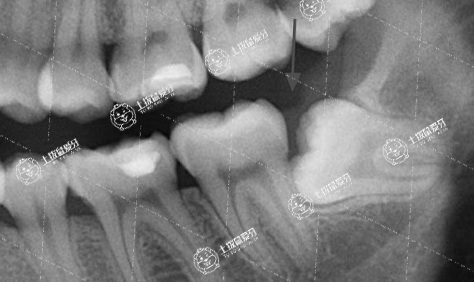

智齒不正常萌出

對(duì)口腔健康有影響,比如把前面的牙齒頂壞了,或者歪著長(zhǎng)或斜著長(zhǎng)了,造成食物殘?jiān)菀浊度模@種情況也建議把智齒拔除。